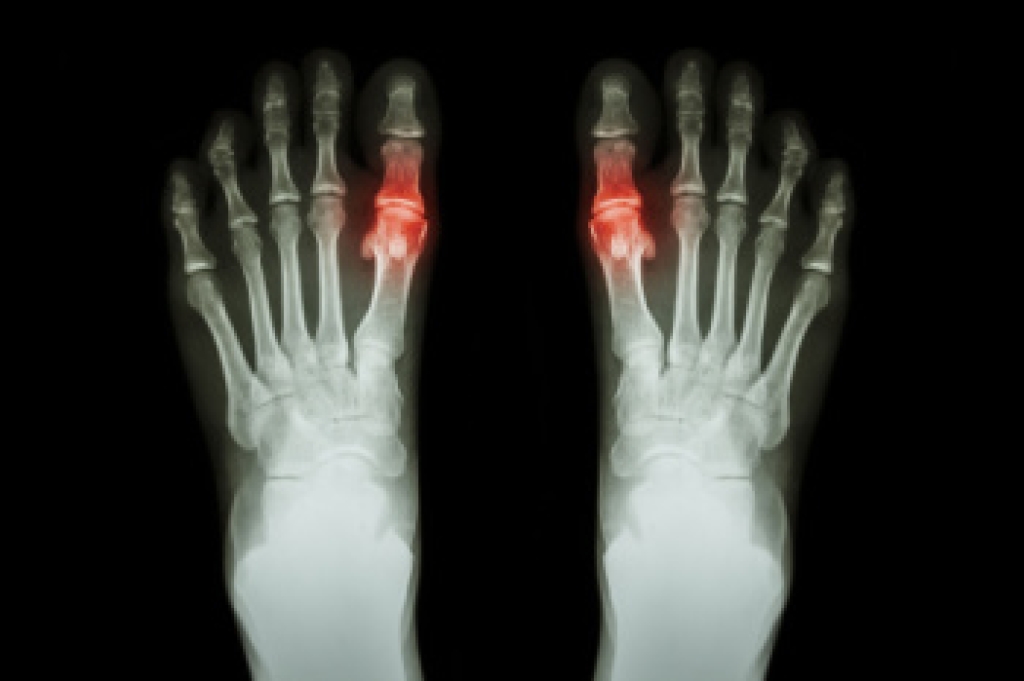

Falls prevention is essential for seniors to maintain safety, independence, and quality of life at home. Falls can lead to serious conditions, such as fractures, head injuries, and foot and ankle harm, that often require long recovery periods. These incidents may also result in loss of independence and the development of a fear of falling, which can limit daily activity. Risk factors include poor balance, weakened muscles, and unsafe home environments. Simple changes like improved lighting can reduce hazards, while falls detection wearables provide immediate alerts for faster assistance. Video monitoring systems can also help address nighttime wandering and improve safety. A podiatrist can help by evaluating foot health, improving stability, and recommending proper footwear. If you or a loved one have injured their foot or ankle from falling, it is suggested that you consult a podiatrist who can provide a diagnosis and guide you on additional falls prevention tips.